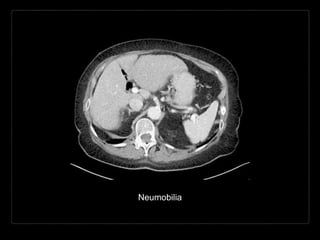

NEUMOBILIA

Acumulación de aire

en el árbol biliar.

Aerobilia

Causas

• instrumenación reciente de la

vía biliar

• CPRE

• colangiografía percutánea o

intraoperatoria

• incompetencia del esfínter de

Oddi

• esfinterotomía (50% al año)

• después del paso de un

cálculo

• cicatrizal (pancreatitis

crónica)

• fármacos (atropina)

• congénito

• anastomosis quirúrgica bilio-

entérica

• colecistoenterostomia

• colédocoduodenostomia

• procedimiento de Whipple.

• fístula bilio-entérica

espontánea

• íleo biliar

• úlcera péptica

• traumático

• neoplasia

(colangiocarcinoma,

ampuloma)

• infección (raro)

• colangitis

• colecistitis

enfisematosa (20%)

• absceso hepático*

• fístula bilio-broncopleural

(rara)

Hallazgos por imagen

• ramificaciones lineales de aire en el hígado

• más prominente en los conductos de mayor calibre

• central

• gas en el sistema venoso portal*

• ramificaciones de aire de calibre pequeño hacia la

periferia